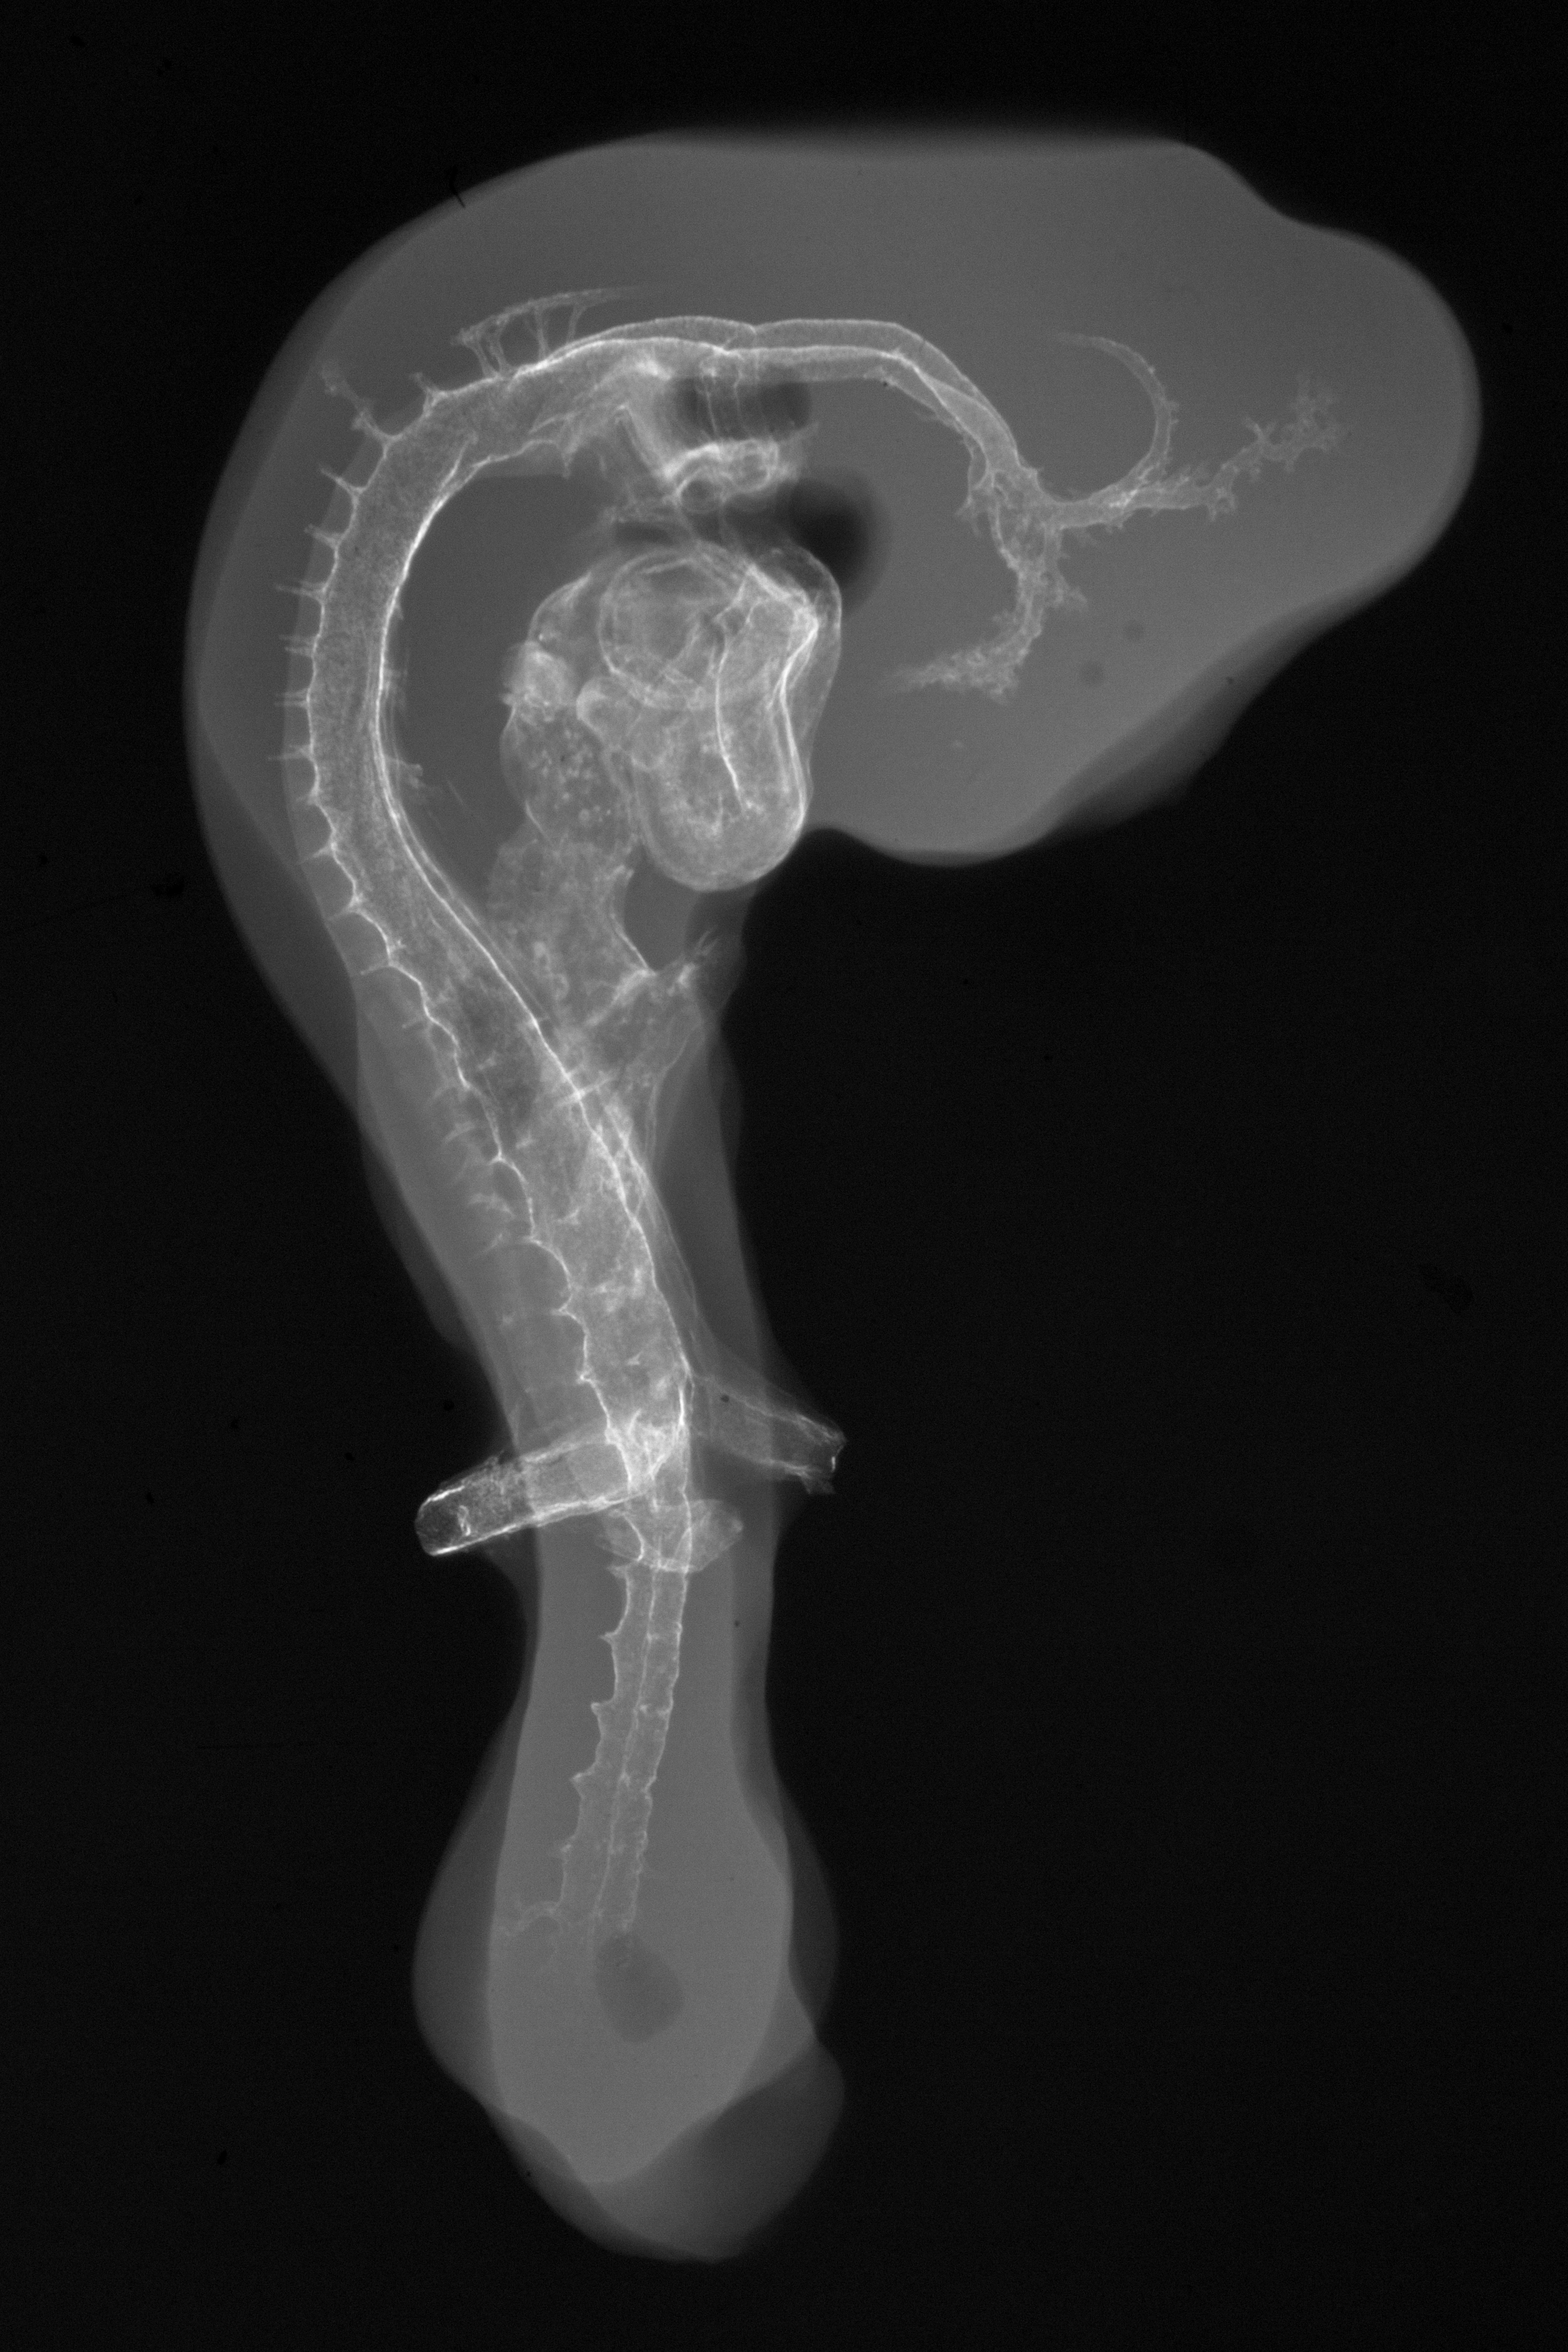

Chick Embryo Microangiography

Hamburger-Hamilton (HH) Stage 19 (approx. 3 - 3.5 days)

Stereo X-Ray Micrographs